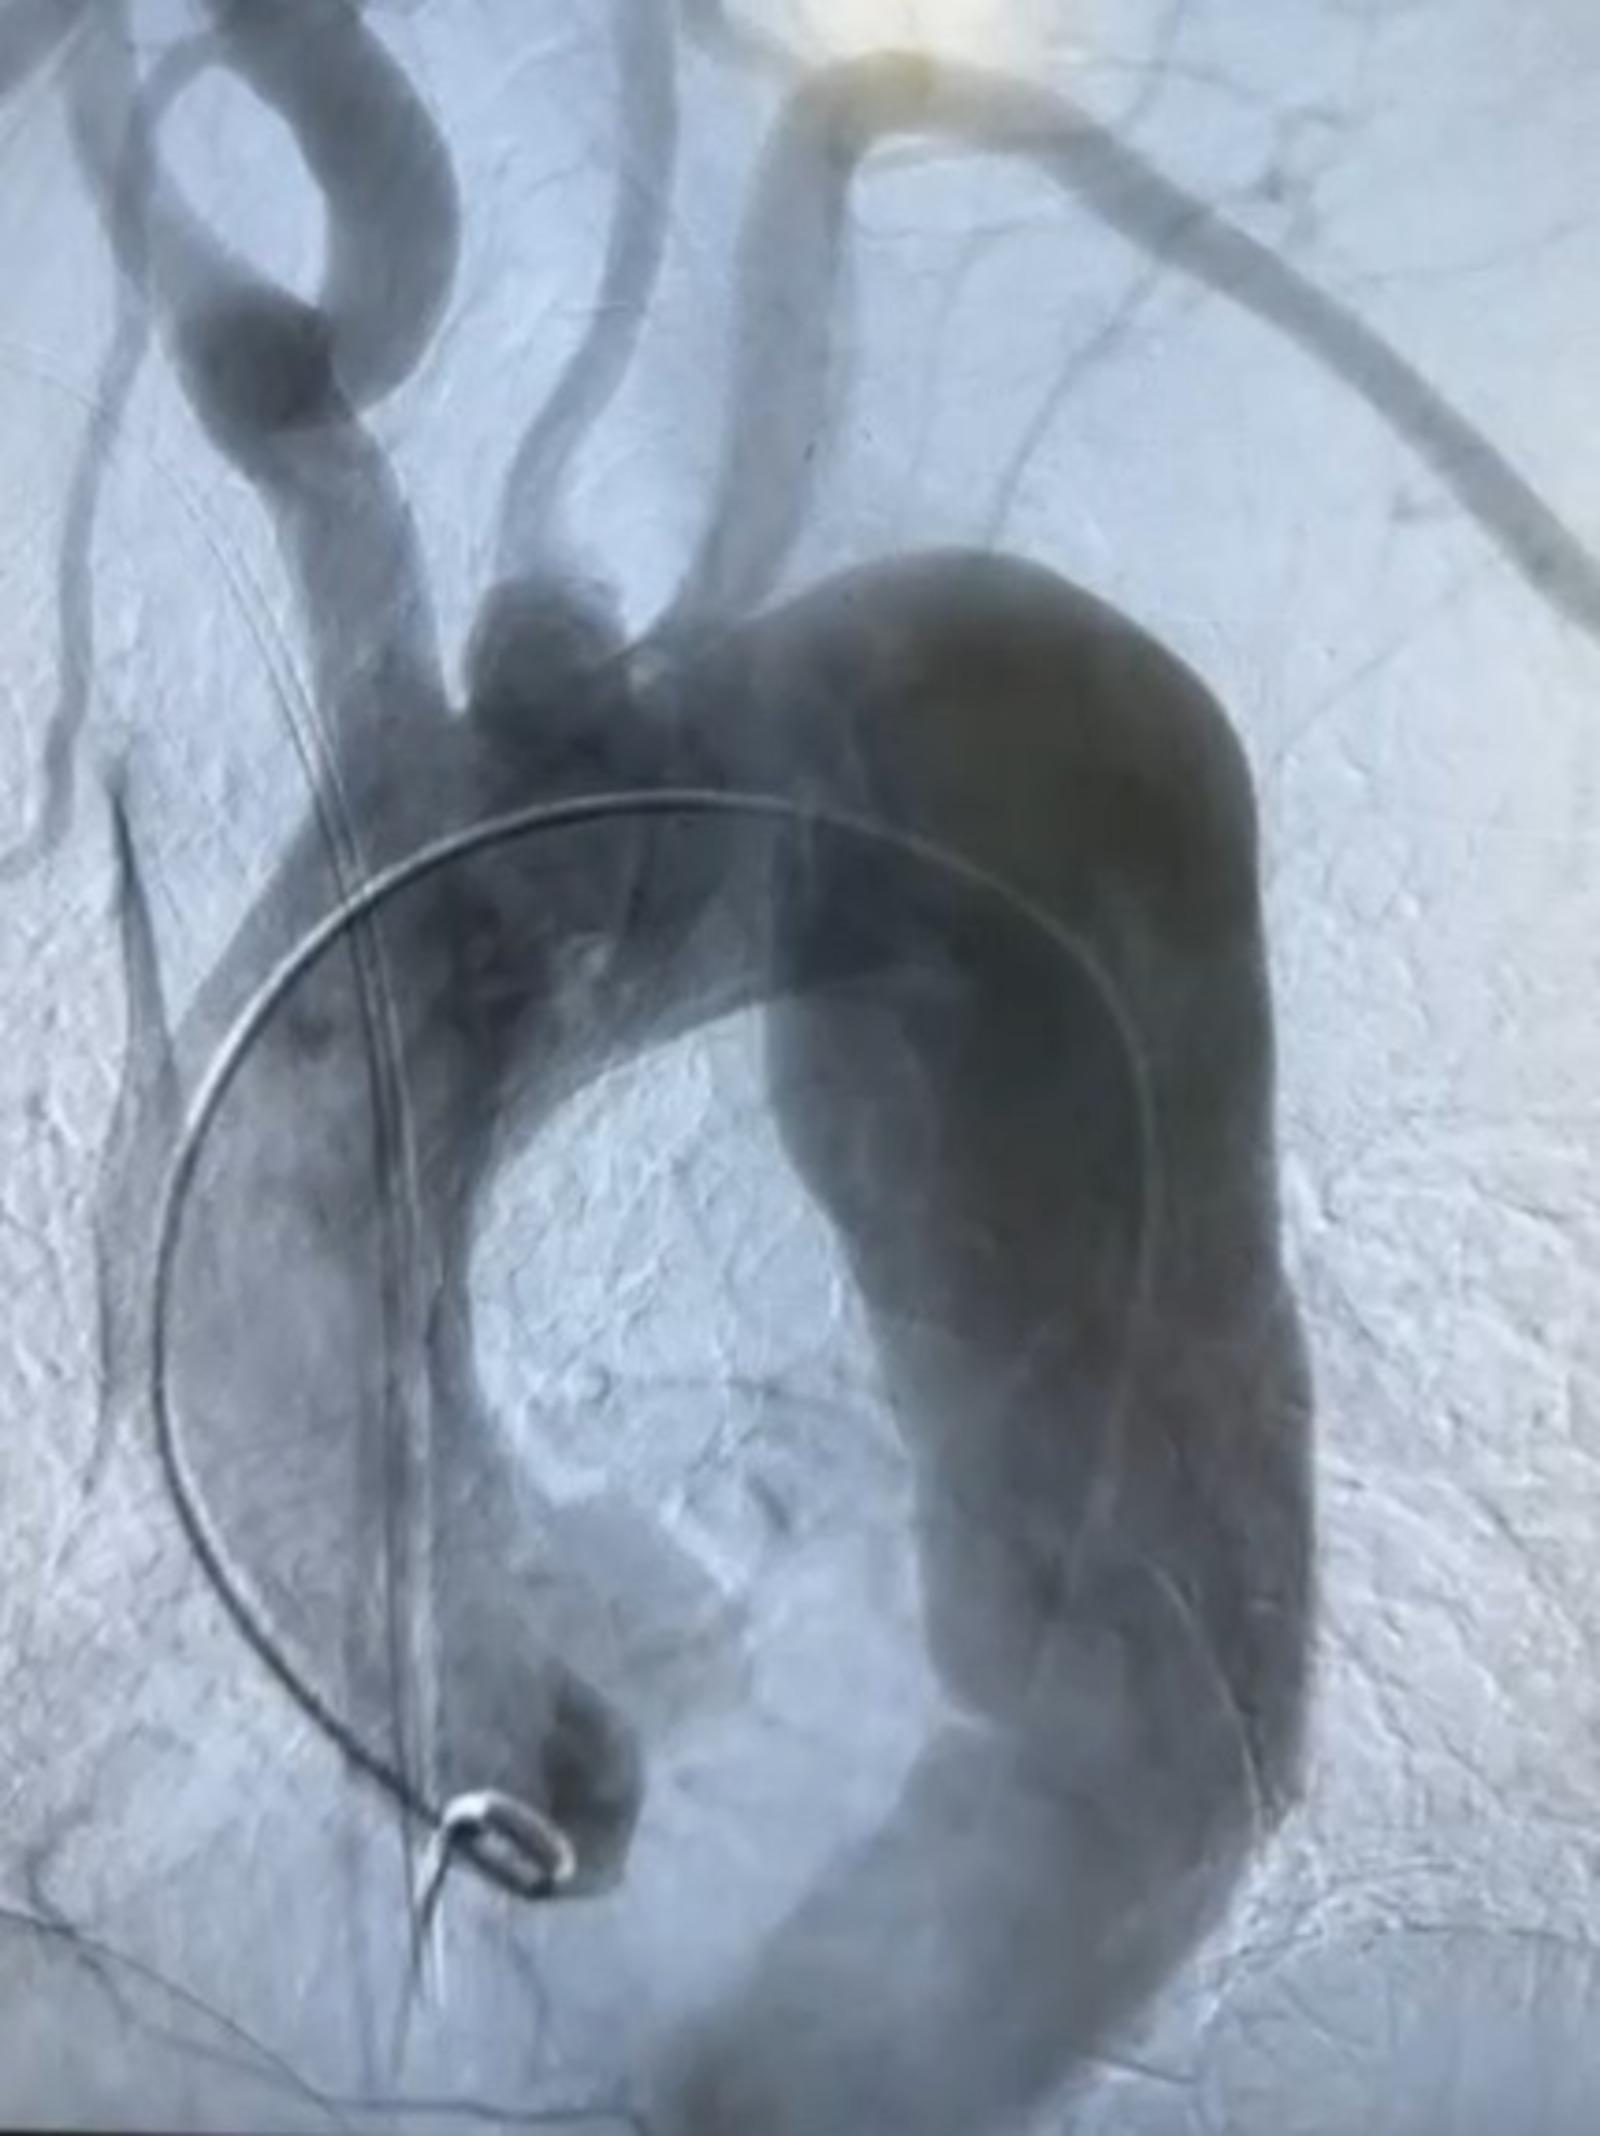

В  Уфе хирурги провели уникальную процедуру. Как сообщила главный врач республиканского кардиологического центра Ирина Николаева, перед операцией, благодаря 3D модели, на  имплантируемой металлической сетке (стен-графт) смоделированы фенестрации под артерии.

Затем стен-графт был заправлен в  систему его установки. Через бедренную артерию эндопротез, с  учётом технических сложностей, был заведён в  просвет аорты, после чего проведена имплантация.

Во  время операции на  контрольной ангиографии наблюдалось полное восстановление просвета аорты. В  составе операционной бригады под руководством заведующего отделением Хафизова участвовали рентгенхирурги Идрисов, Катаев, анестезиолог Челотканов, операционная медсестра Хайдарова.